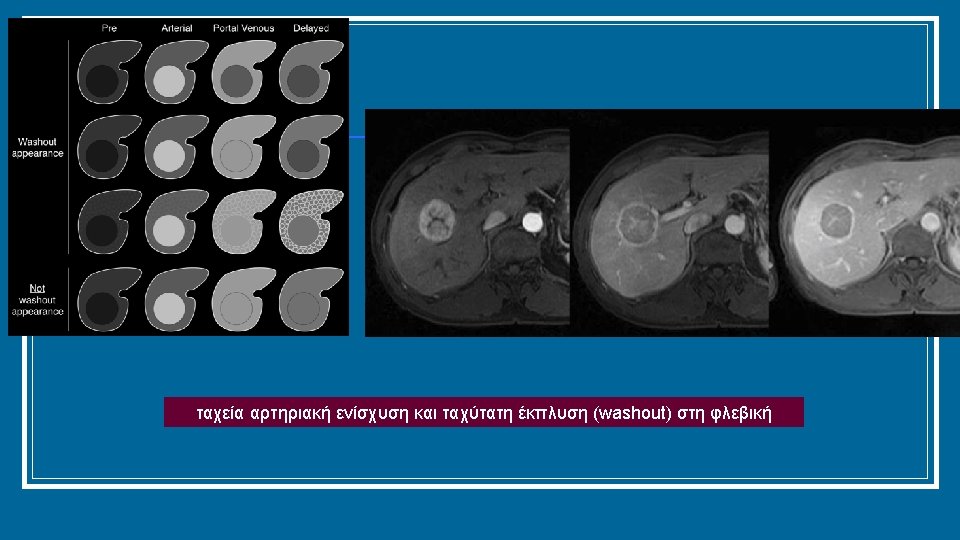

Διάγνωση σε κιρρωτικό ήπαρ (σε μη κιρρωτικούς, επιβεβαίωση με βιοψία) Mass/nodule at imaging <1 cm >1 cm Repeat US at 4 months Multiphasic contrast-enhanced CT or MRI, * or gadoxetic-enhanced MRI † Growing/changing pattern Stable‡ 1 positive technique: HCC imaging hallmarks No Biopsy unclear: Consider re-biopsy ‖ Yes Use other modality: multiphasic contrast-enhanced CT or MRI, * or gadoxetic-enhanced MRI, † or contrast-enhanced ultrasound § 1 positive technique: HCC imaging hallmarks Non-HCC malignancy/ benign No Yes Biopsy HCC *Using extracellular MRI contrast agents or gadobenate dimeglumine; †Diagnostic criteria: APHE and washout on the portal venous phase; ‡Lesion <1 cm stable for 12 months (three controls after 4 months) can be shifted back to regular 6 -month surveillance; §Diagnostic criteria: APHE and mild washout after 60 seconds; ‖Optional for centre-based programmes EASL CPG HCC. J Hepatol 2018; doi: 10. 1016/j. jhep. 2018. 03. 019